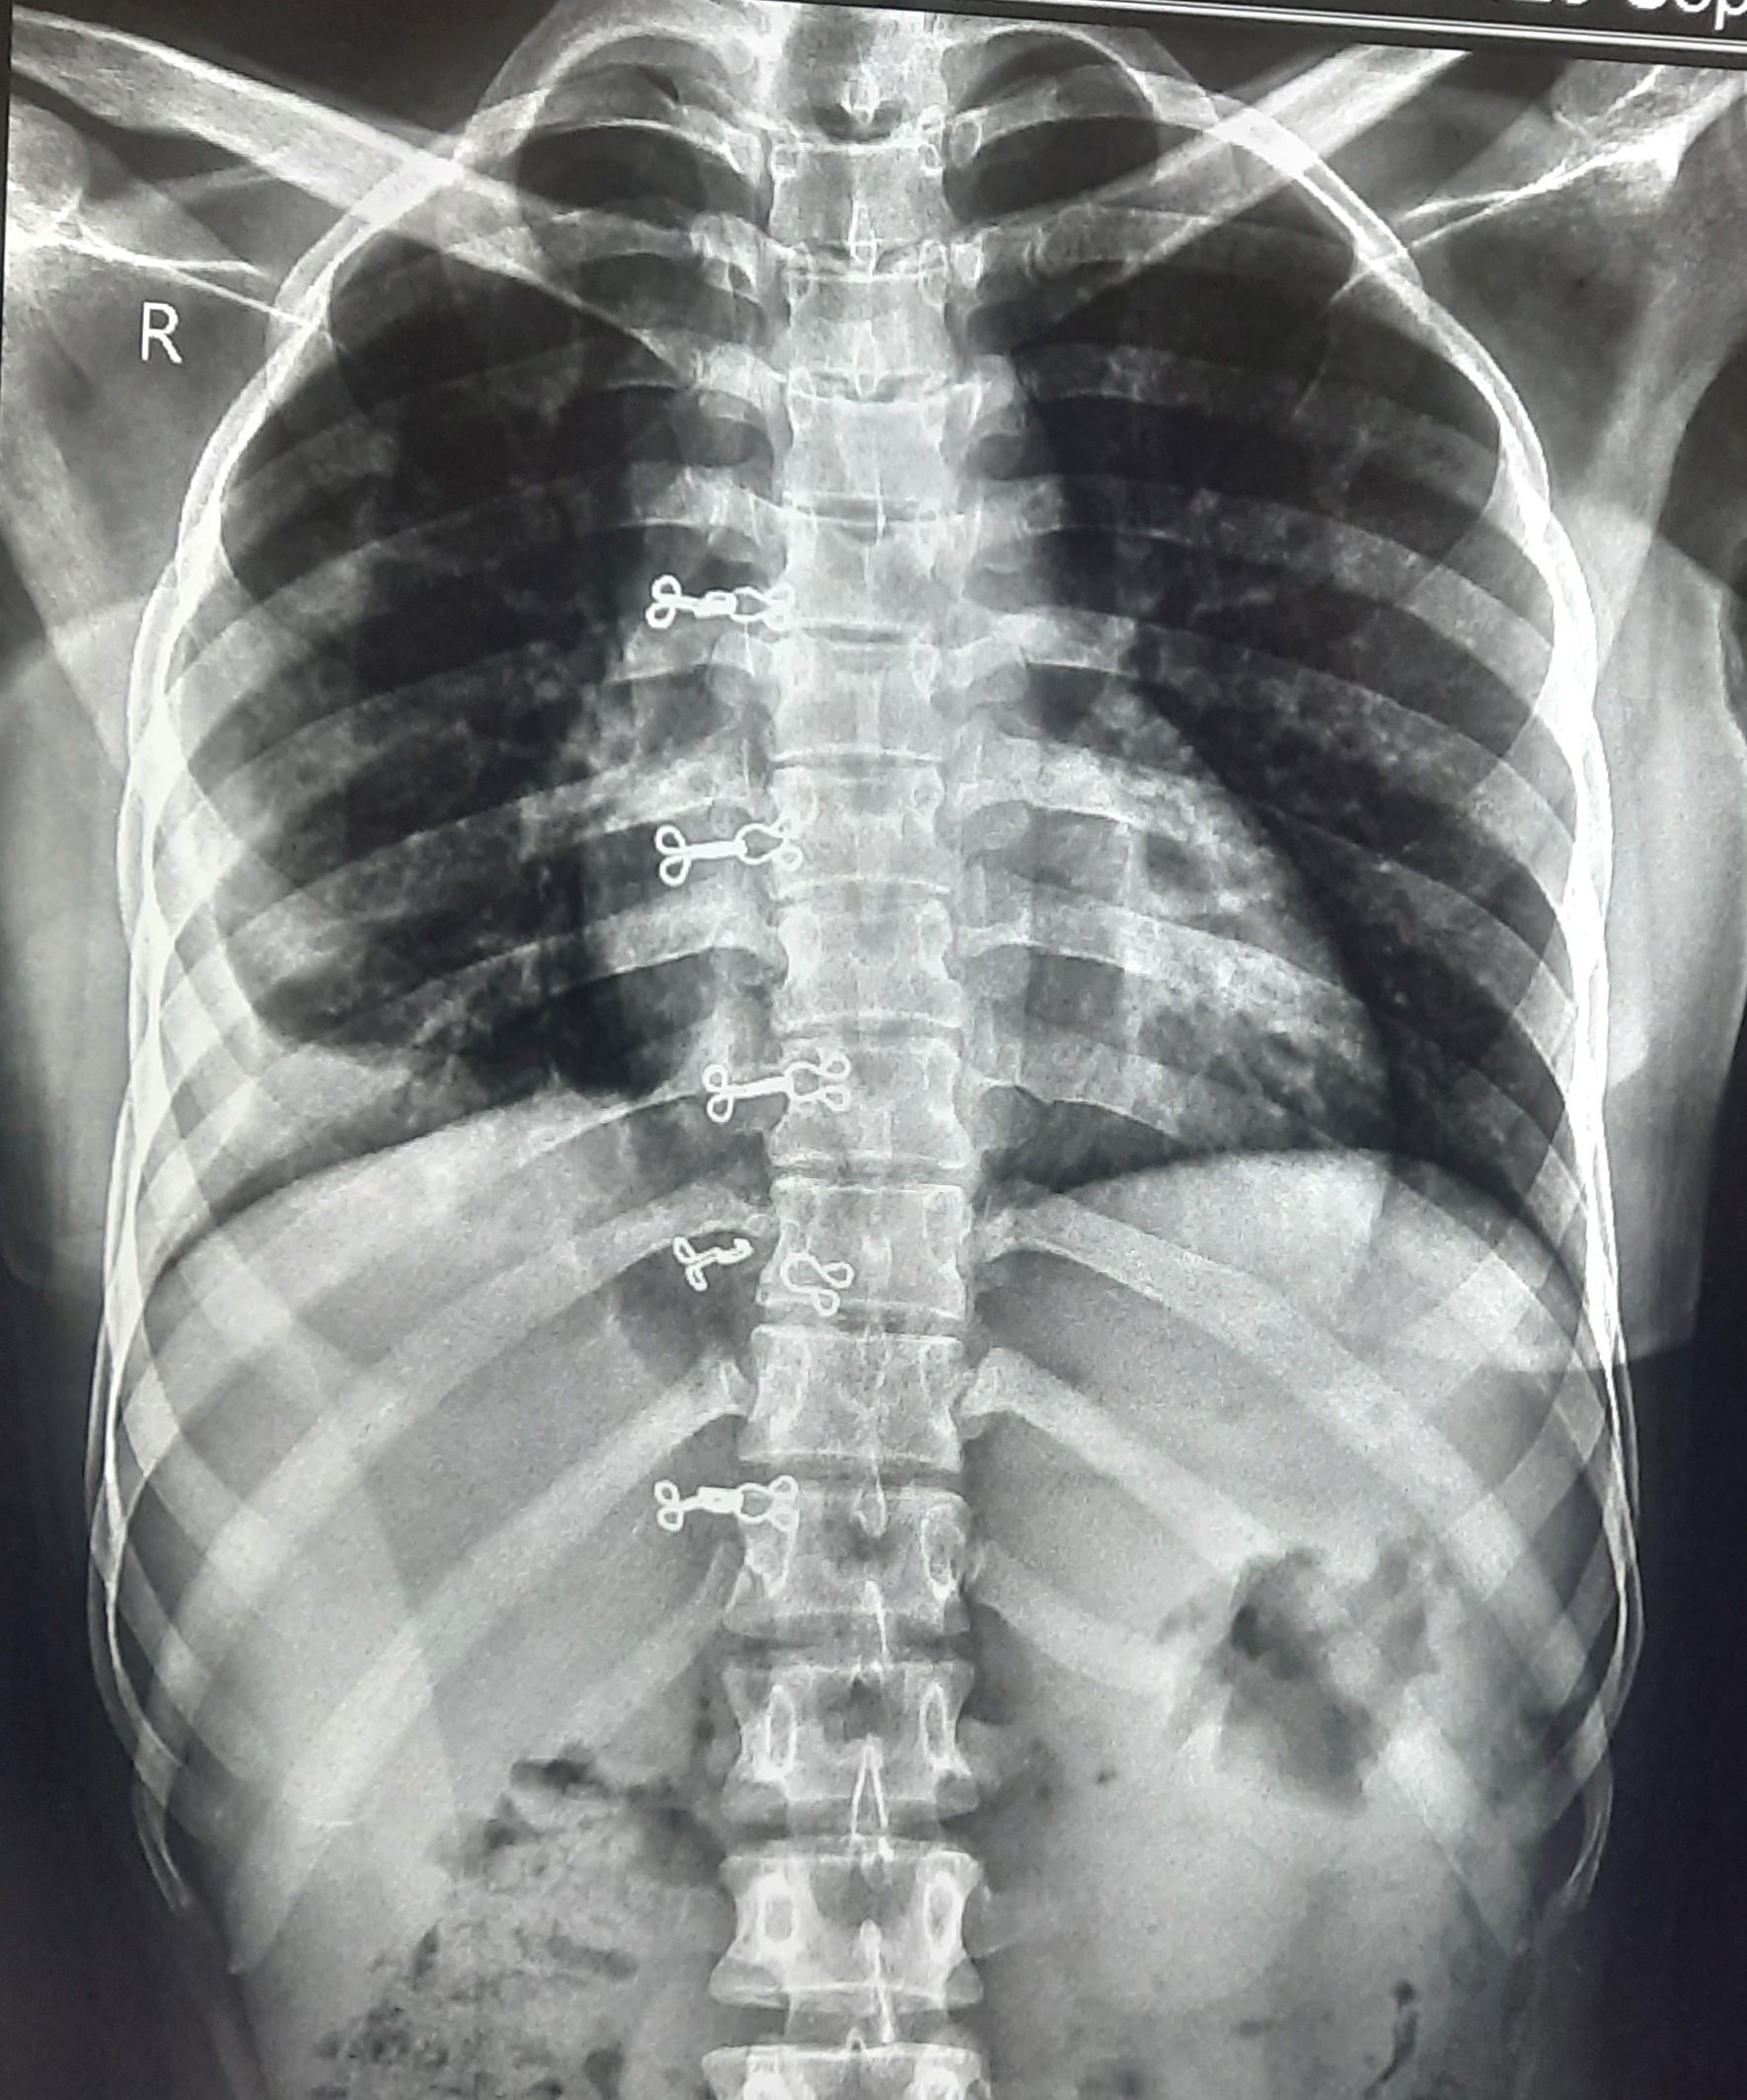

| 60 | IGGMC, Nagpur, Nagpur | P2 | 29-4412 | Ritesh Uikey | Consent taken on Paper | 30 Yrs. |

Provisional Diag : Pulmonary Tuberculosis

Final Diag : Pulmonary Tuberculosis |

TB Case (Confirmed) | Bilateral Lung Infiltration Present & Right Upper Zone Cavity Present | Abnormality visible on x-ray |